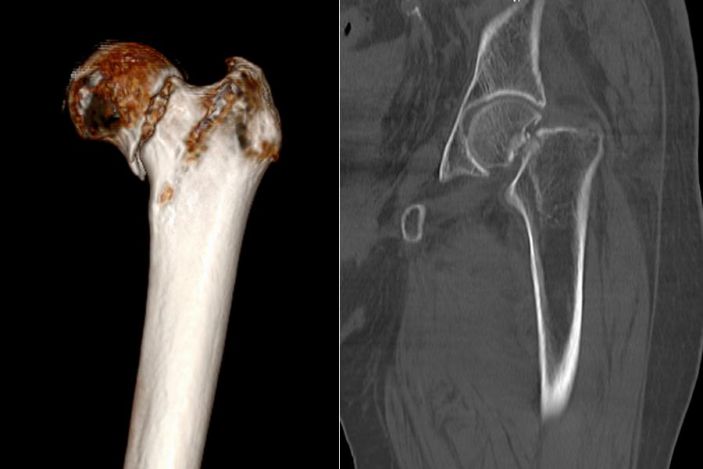

經過CT檢查發現老人家的左股骨頸骨折。此外還伴有老年性骨質疏松、高血壓病、低鈉低鉀血症等疾病。骨科吳志斌主任随即請内科、麻醉科專家會診。予監控血壓、血糖,抗骨質疏松、營養心肌等對症治療。待患者病情穩定、可耐受手術後進行手術治療。

吳志斌主任通過CT+三維重建先行拟定詳細手術方案,提前做了精心準備。根據患者的年齡特征,爲其選擇最佳的半髋置換方案,并采用雙動人工股骨頭,提高活動範圍,減少髋臼磨損。

△術前